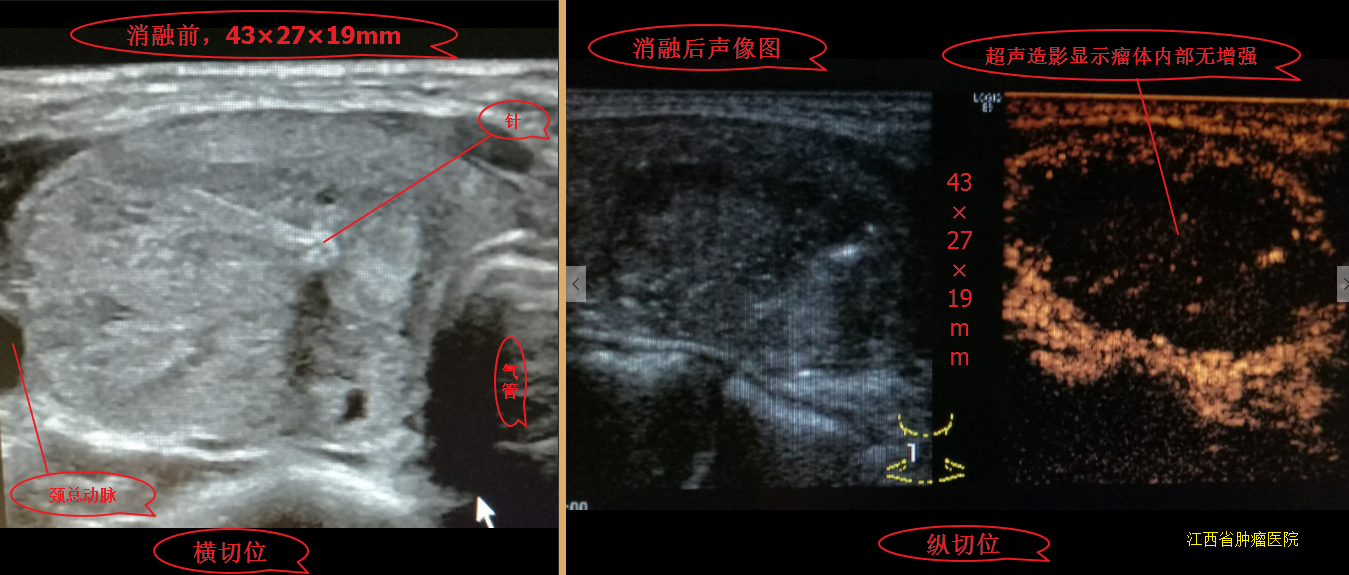

甲状腺结节微波消融术后,随访效果图!

1358x527 - 686KB - PNG